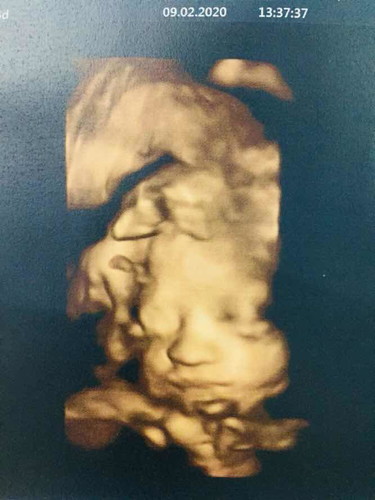

26 สัปดาห์ 5 วัน

ดีใจด้วยค่ะแม่ แลดูตรงสันจมูก

กำลังตั้งครรภ์